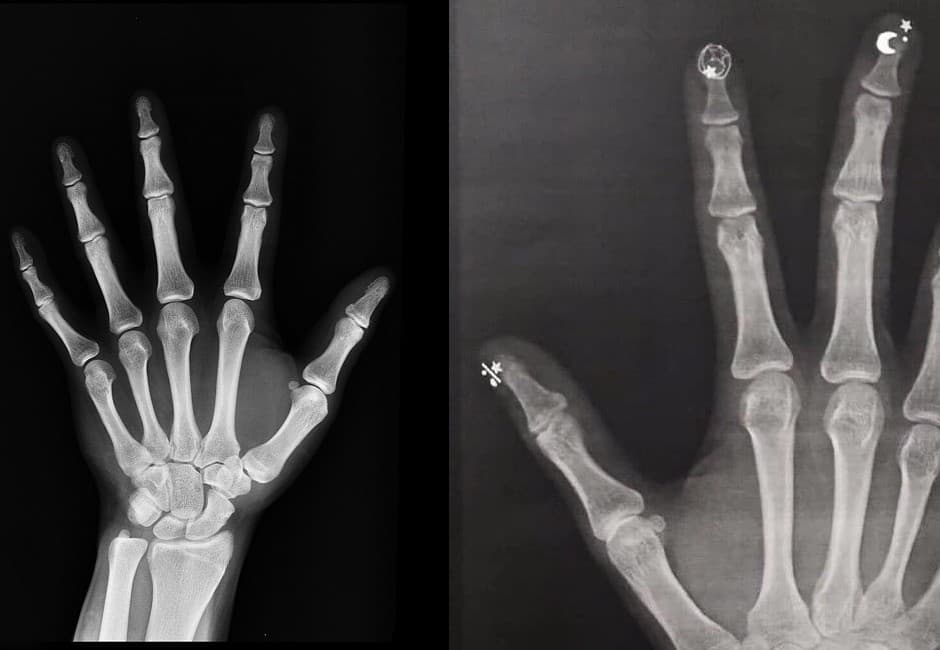

許多人都有被門夾傷手指、腳趾的經驗,小則痛到懷疑人生,痛完沒事倒還好,但嚴重的話可能傷及骨頭,造成骨裂甚至是骨折。最近就有一名網友表示自己老婆不小心被門夾傷,保險起見決定去醫院進一步詳細檢查,同時照X光,不過照出來的結果卻連醫師都驚呆「從沒看過這樣的骨骼」。

從照片中可以看到,照出來的X光片的手指末端,每一隻手指都有星星或是月亮的黑影,另不少網友看了驚訝表示「美少女戰士4ni」、「你老婆月光仙子喔」、「表示妳的老婆至少會用五種魔法」、「最近叫她別彈手指,不然會出大事」,直呼這樣的結果實在讓人感到不可思議。

不過也有老司機出面解答,說會呈現這樣的現象應該是因為有做「光療指甲」,由於指甲上方的裝飾會阻擋X光,才會照出各種不同形狀的陰影,解釋「這表示彩繪指甲上的塗料含有金屬成份,會反射X光而已」,要大家別太擔心。事實上,這張圖其實已經在網路上流傳已久,最近因為被分享到臉書社團,才又意外引來大家的討論。